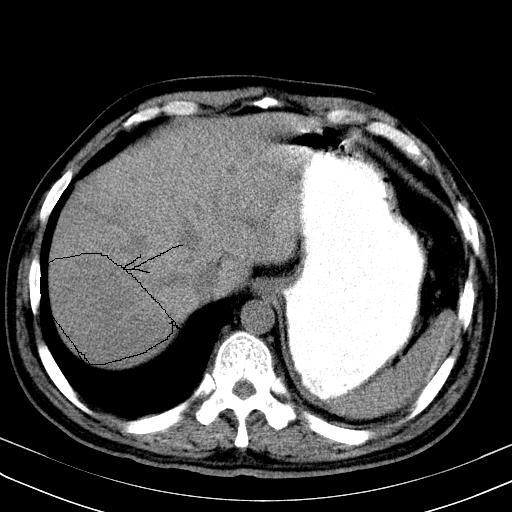

标题: 肝脏

大家看看肝脏右叶片状低密度影是什么改变啊?

淋巴瘤?肝脏请增强后说啊

多发肿大淋巴结影,肝内改变需结合强化观察

多发肿大淋巴结影,肝内改变需结合强化观察。